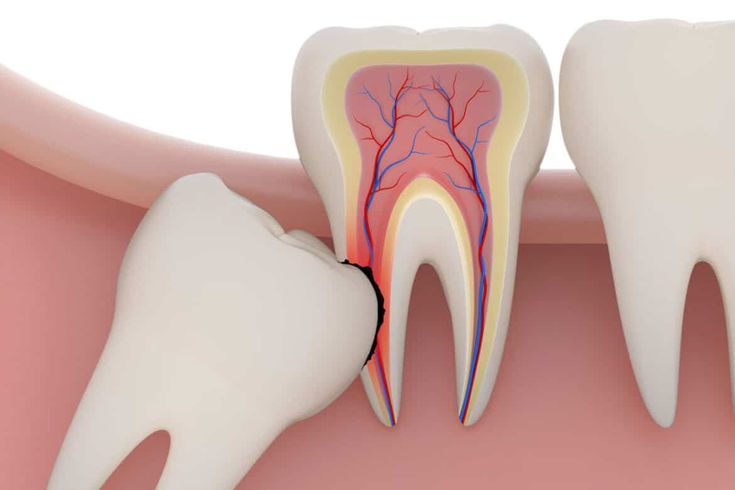

Wisdom teeth are the last set of molars to erupt. Removal is a common surgical procedure for teeth that are impacted (stuck beneath the gum line) or are causing crowding, pain, or recurrent infection in the back of the jaw.

Removing problematic wisdom teeth prevents serious issues such as shifting of other teeth, damage to adjacent molars, severe infection, and the formation of cysts or tumors in the jaw. It is a preventative measure for long-term oral health.

Same as Tooth Extraction: Stick to soft foods for several days. Avoid straws, smoking, spitting, and crunchy/chewy foods to ensure the surgical sites heal properly and to prevent the painful condition of dry socket.